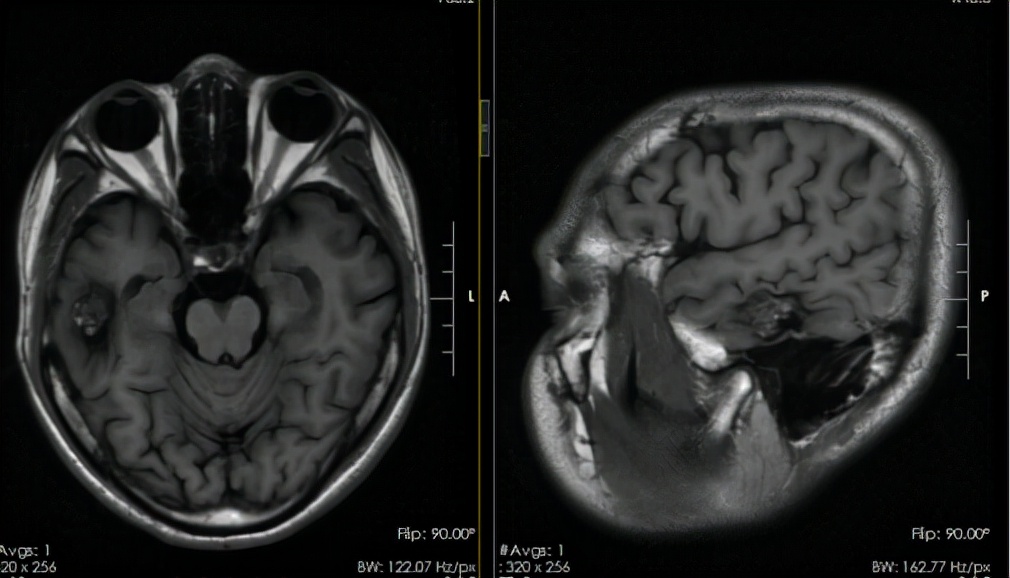

到去年11月底,张先生如期返院复查。当时的颅脑CT检查结果提示其右颞海绵状血管瘤有少量出血。“虽然目前没有出现症状,但病灶反复出血会对脑功能造成损害,建议尽快手术。”听了吴杰的分析后,张先生决定再接受手术切除右颞海绵状血管瘤。

术前头颅MRI:右侧颞叶海绵状血管瘤伴出血